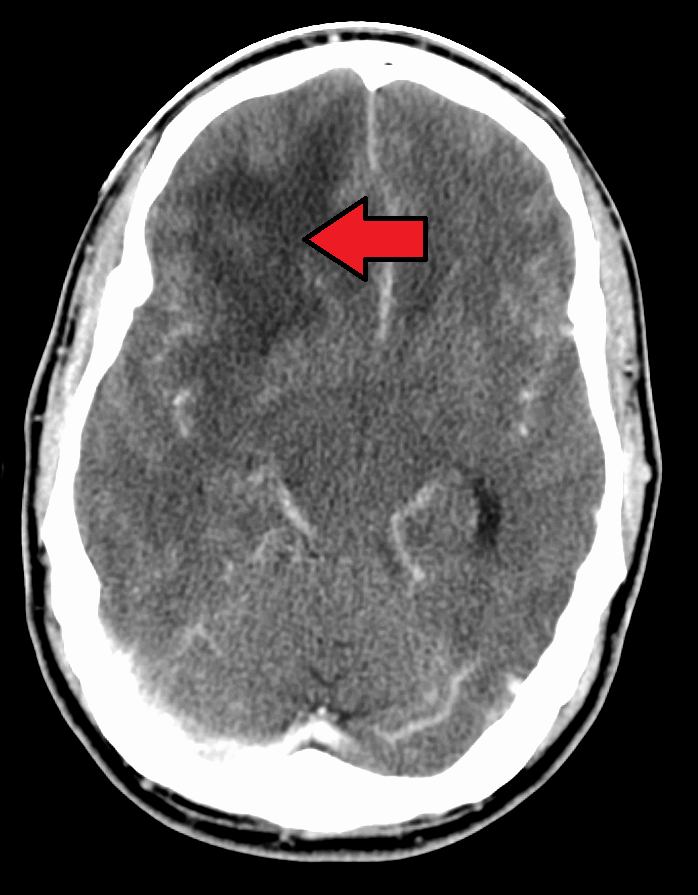

Radiology of oligodendrogliomas typically show a calcified tumor involving the central nervous system (CNS).

Oligodendrogliomas typically affects the frontal lobe.

Oligodendrogliomas may cause seizures due to mass effect.